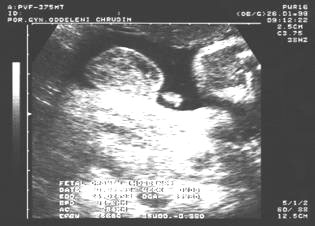

9. týden: plodové vejce

9.týden